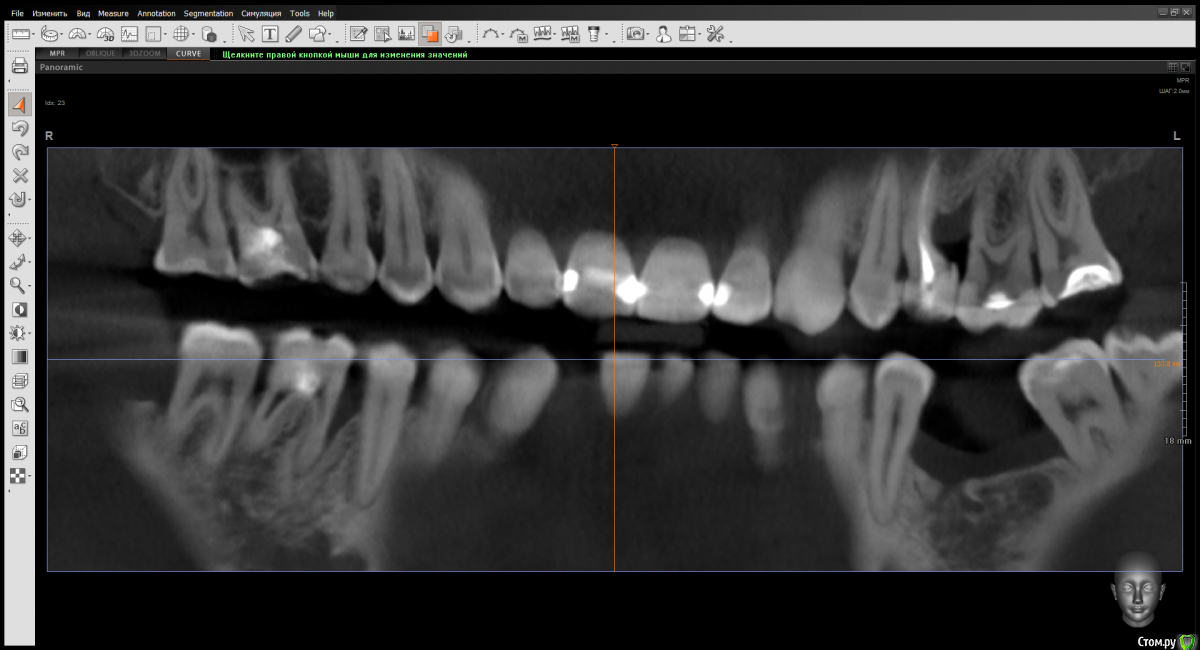

Doctor Vlad Опубликовано 22 марта, 2020 Автор Поделиться Опубликовано 22 марта, 2020 Диагноз какой?Хронический периодонтит 25 Кариес корня 26 Аномалия формы корня 25 локализованный пародонтит или рецессия десны 25 26 оьласти. кость ушла...за ней десна и по накатанной Ссылка на комментарий

Doctor Vlad Опубликовано 22 марта, 2020 Автор Поделиться Опубликовано 22 марта, 2020 у него внизу тоже сюрпризы .может перегрузка. явного воспаления в десне нет. кармана тоже нет. Ссылка на комментарий

krokomot Опубликовано 22 марта, 2020 Поделиться Опубликовано 22 марта, 2020 Склоняюсь к перфе или трещине 5ого, если причину убрать то кость можно вернуть, если дефект настолько локализованный и по десне норм. Ссылка на комментарий

Дмитрий Л. Опубликовано 23 марта, 2020 Поделиться Опубликовано 23 марта, 2020 Там просто пломбы с нависающим краем. Ссылка на комментарий

krokomot Опубликовано 23 марта, 2020 Поделиться Опубликовано 23 марта, 2020 Там просто пломбы с нависающим краем.при такой кривизне изгиб канала вполне мог быть пропилен ручным инструментом. Нужно посмотреть на горизонтальном срезе. Ссылка на комментарий

Doctor Vlad Опубликовано 25 марта, 2020 Автор Поделиться Опубликовано 25 марта, 2020 Там просто пломбы с нависающим краем.и аномалия формы корня 25. тоже видимо сыграло. и перегруз по прикусу Ссылка на комментарий

Doctor Vlad Опубликовано 25 марта, 2020 Автор Поделиться Опубликовано 25 марта, 2020 Склоняюсь к перфе или трещине 5ого, если причину убрать то кость можно вернуть, если дефект настолько локализованный и по десне норм.по десне антинорм. там карандаш пройдет Ссылка на комментарий

krokomot Опубликовано 25 марта, 2020 Поделиться Опубликовано 25 марта, 2020 Дефект можно попытаться закрыть полностью вылечив 2.5 и 2.6. Исключить проблемы с корнями зубов. Как? Есть много методик. Ссылка на комментарий

dentikl Опубликовано 27 марта, 2020 Поделиться Опубликовано 27 марта, 2020 аргументируйтепредполагаю перф на колене .А учитывая карман,выдвижение и тд-удалить. Ссылка на комментарий